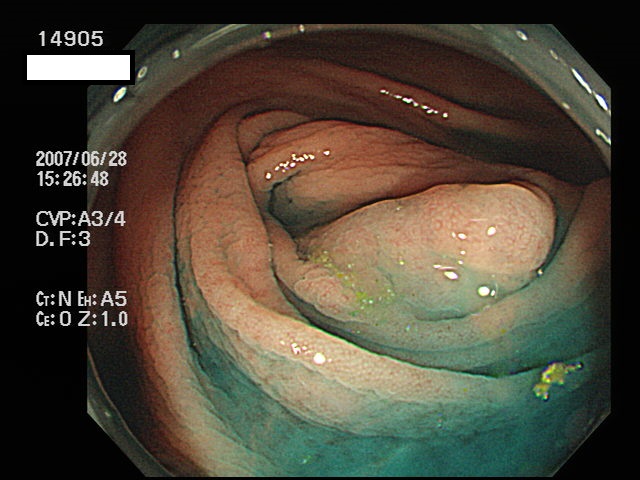

虫垂開口部の過形成ポリープ(SSAP)の例

一般に虫垂過形成ポリープが見られる方は「大腸の他の部位にもポリープ(特にSSAP)が見つかる可能性が非常に高い」のです。つまり「危険な腸である」という警告灯になるのです。虫垂は大腸の一番奥ですから「観察のスタート地点」です。ここで警告灯が出ることは非常に有益な訳です。